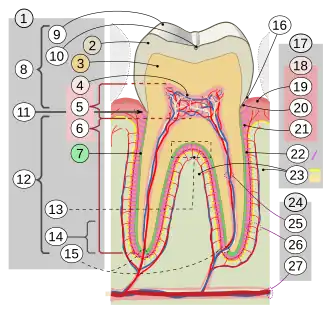

1-dent 2-émail dentaire 3-dentine 4-pulpe dentaire 5- 6- 7-cément 8-couronne 9-cuspide 10-sillon 11-collet 12-racines 13-furcation radiculaire 14-apex 15-foramen apical 16-sulcus gingivae 17-parodonte 18-gencive 19-gencive libre 20- 21-gencive attachée 22-ligament alvéolo-dentaire 23-os alvéolaire 24-vaisseaux et nerf… 25-…dentaires 26-…paradontaux 27-canal alvéolaire

Une dent est constituée d'une structure de dentine lui donnant sa forme globale et qui contient une cavité dentaire.

Au niveau de la couronne, la dentine est recouverte d'une couche d'émail dentaire. Au niveau de la racine, elle est recouverte d'une couche de cément.

La cavité dentaire s'ouvre vers l'extérieur au niveau du ou des apex des racines de la dent par les foramens apicaux qui se poursuivent par les canaux radiculaires le long de chaque racine. Les canaux radiculaires convergent dans la couronne pour former la cavité de la couronne dentaire. La cavité dentaire renferme la pulpe de la dent.

La racine est implantée dans l'os auquel elle est reliée par le ligament alvéolo-dentaire formant une syndesmose dento-alévéolaire (ou improprement gomphose).